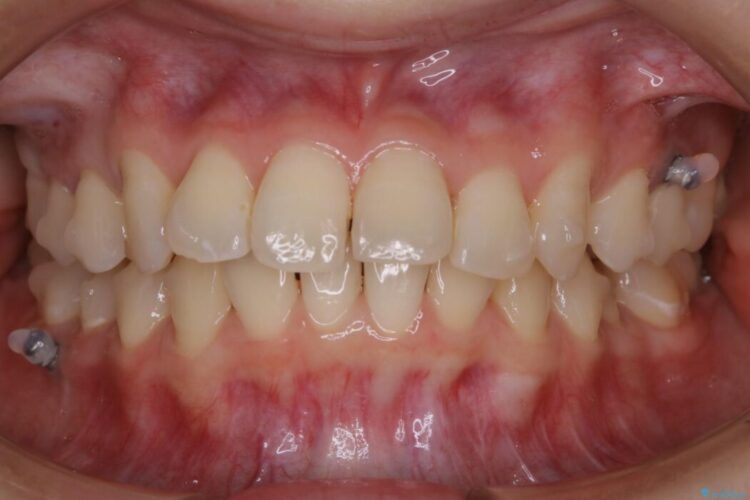

【20代女性】ブライダルに向けた矯正できれいなスマイルラインへ

- 治療期間:1年10ヶ月

- 矯正装置:インビザライン コンプリヘンシブパッケージ

ガタつきの度合いから抜歯は不要と判断しましたので、マイクロインプラントを用いて歯全体を遠心移動させていくことでねじれや噛み合わせのズレを改善していく計画を立てました。